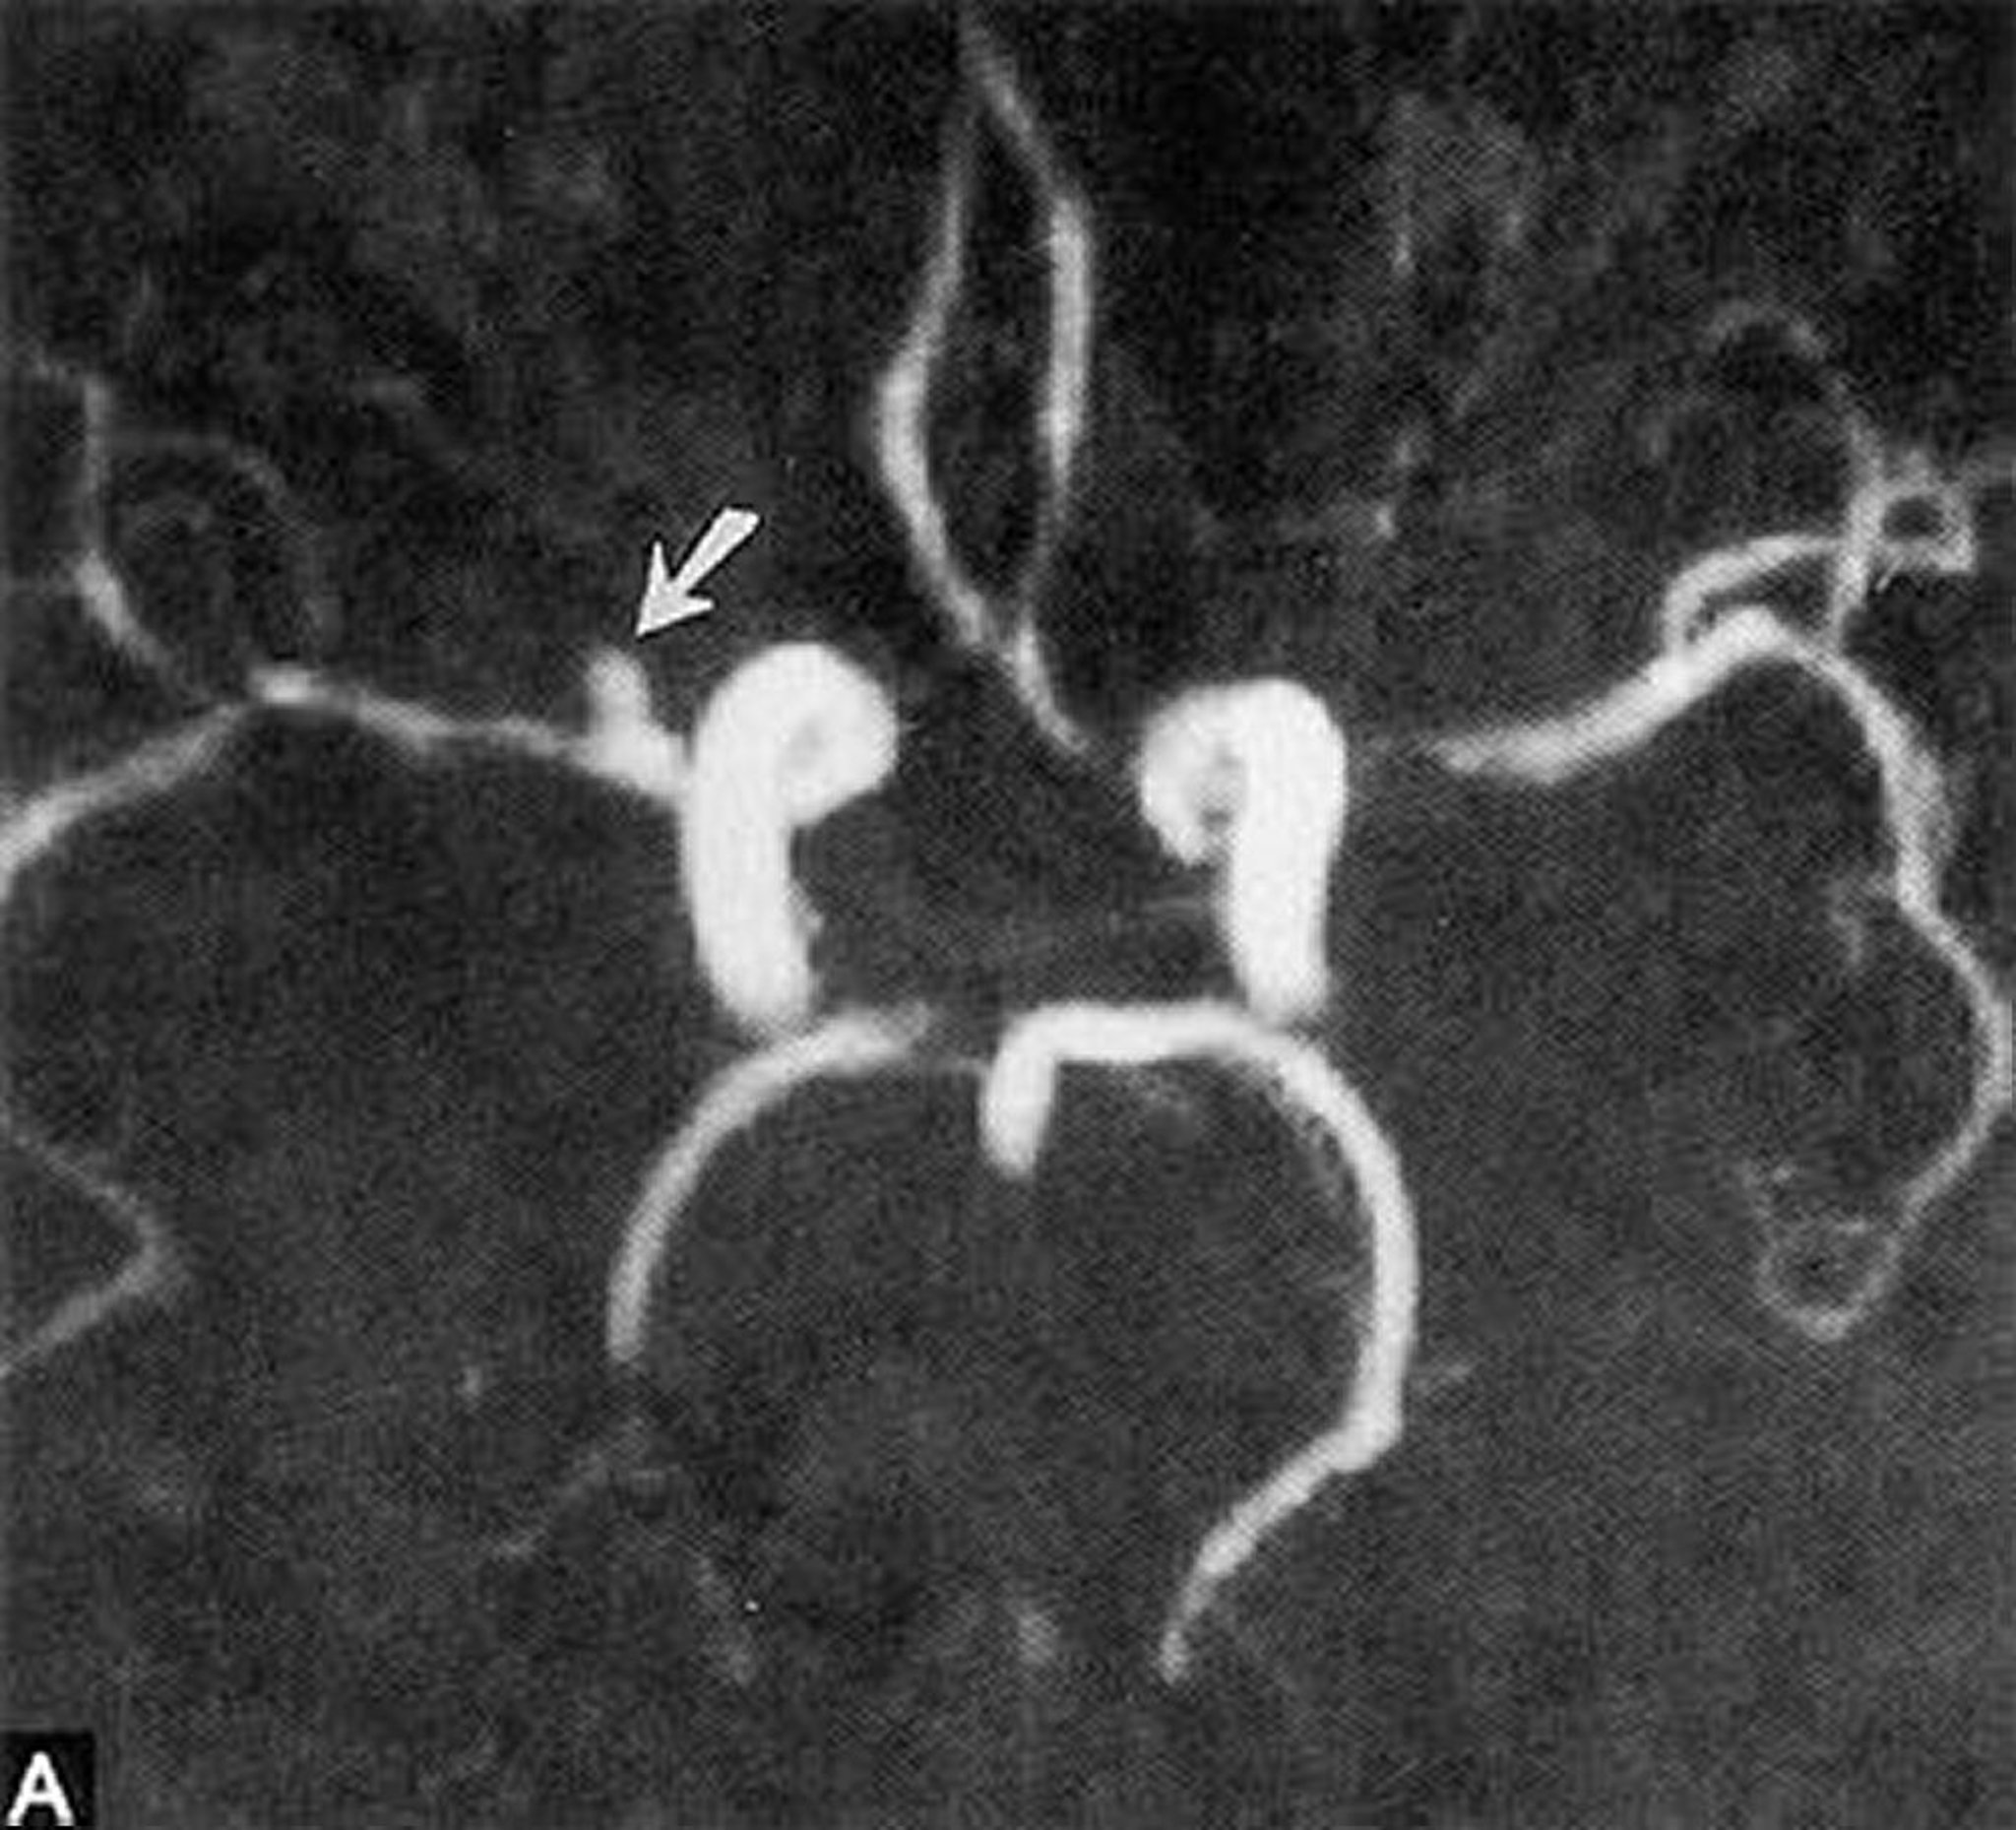

Aneurisma sacculare

Questa angiografia a risonanza magnetica mostra un piccolo aneurisma sacculare dell'arteria cerebrale media destra orizzontale (freccia).

By permission of the publisher. From Ritter A, Hayman L, Charletta D. In Atlas of Cerebrovascular Disease. Edited by PB Gorelick and MA Sloan. Philadelphia, Current Medicine, 1996.